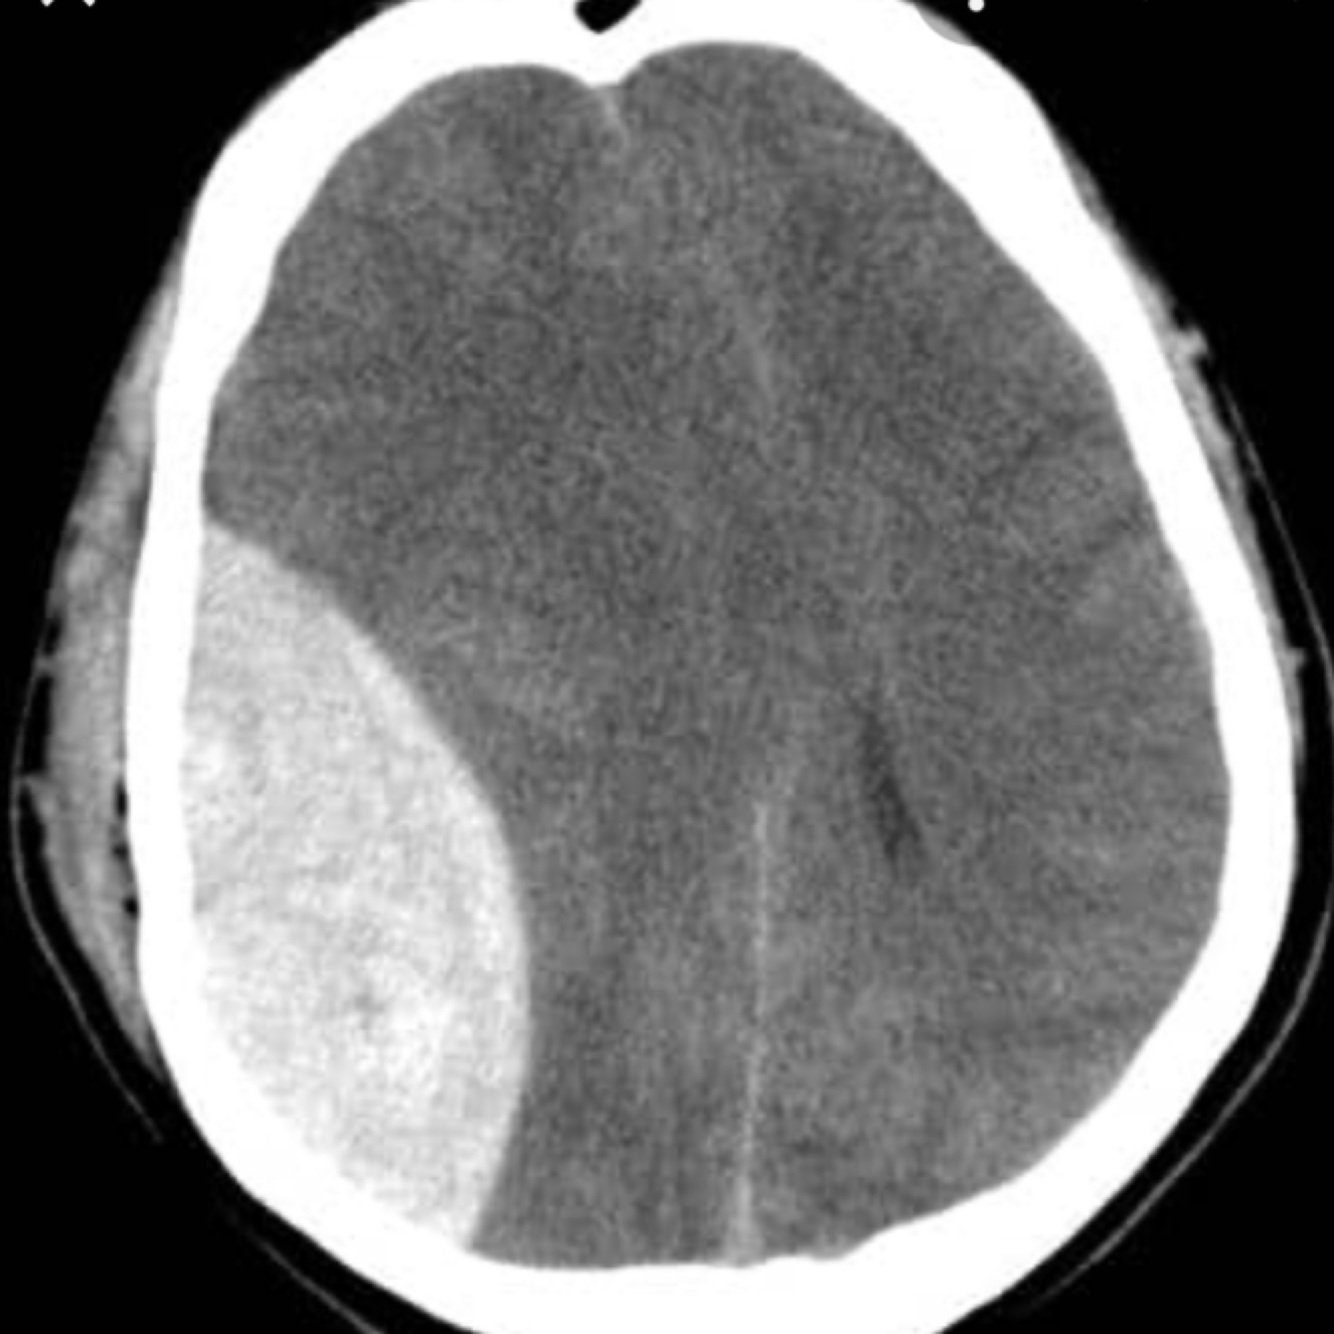

14

Q

Subdural haemorrhage

15

A

Acute subdural haemorrhage

Haemorrhage flows contour of skull as not limited by skull sutures

Subdural haemorrhage is caused by rupture of the bridging veins in the outermost meningeal layer. They occur between the dura mater and arachnoid mater. On a CT scan they have a crescent shape and are not limited by the cranial sutures (they can cross over the sutures).